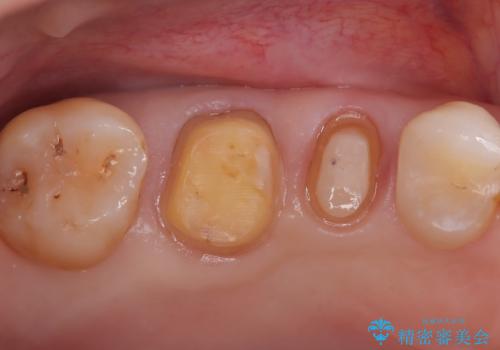

- 右上の奥歯(5番・6番)の被せ物の適合が悪く、歯ぐきが腫れやすい状態でした。患者さんご自身も「物がつまりやすい」「違和感がある」との訴えがあり、レントゲンと視診を行ったところ、被せ物の下にむし歯が進行していることが判明しました。特に右上5番は、神経の治療(根管治療)が過去に行われていましたが、根の先に炎症が残っており、治療のやり直しが必要と判断しました。

まずは両歯の古い被せ物を慎重に除去し、中のむし歯を確認しました。右上5番は神経の治療のやり直し(再根管治療)を行い、細菌感染を取り除いたうえで、根の中を密に封鎖しました。治療中は仮歯を入れて審美性と機能性を保ちつつ、歯ぐきの状態も改善していきました。